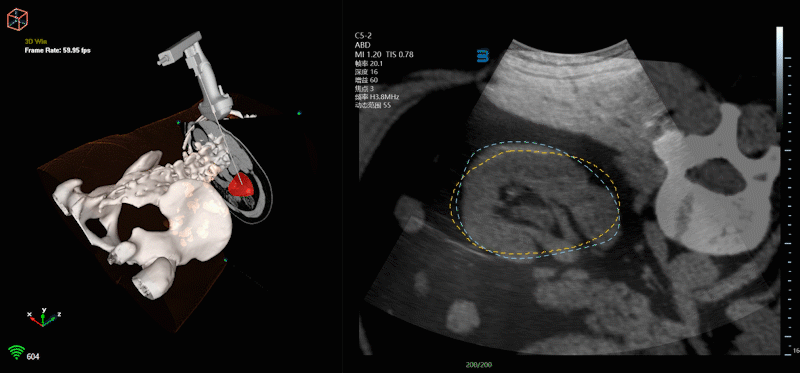

Venus1多模态影像融合超声系统:

通过超声实时性与CT/MRI影像分辨率高特点实时快速精准融合,更清晰直观展现人体解剖结构,结合电磁导航技术在3D模态下做术前路线规划,利用AI(人工智能)辅助针尖动态识别更精准引导手术通道的路径建立,同时多模态影像2D-3D联动与AI配准下更精准的实时呈现病灶位置等创新技术,对降低前列腺穿刺活检漏诊率、肿瘤精准消融、复杂肾结石病例经皮肾镜碎石取石术(PCNL)目标盏定位、降低并发症等具有重要临床应用价值。